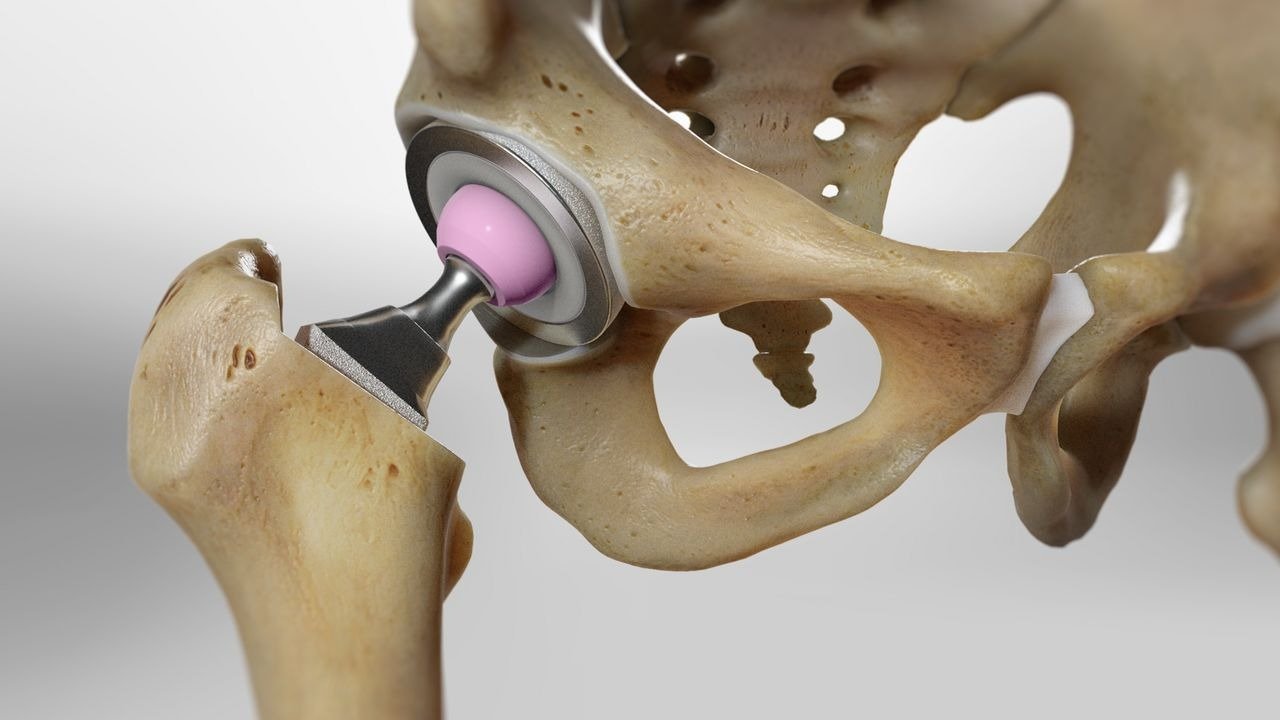

Kidney Transplant

Kidney transplant is one of the most commonly performed procedures in India. It is recommended for patients with chronic kidney disease or kidney failure who are dependent on dialysis.